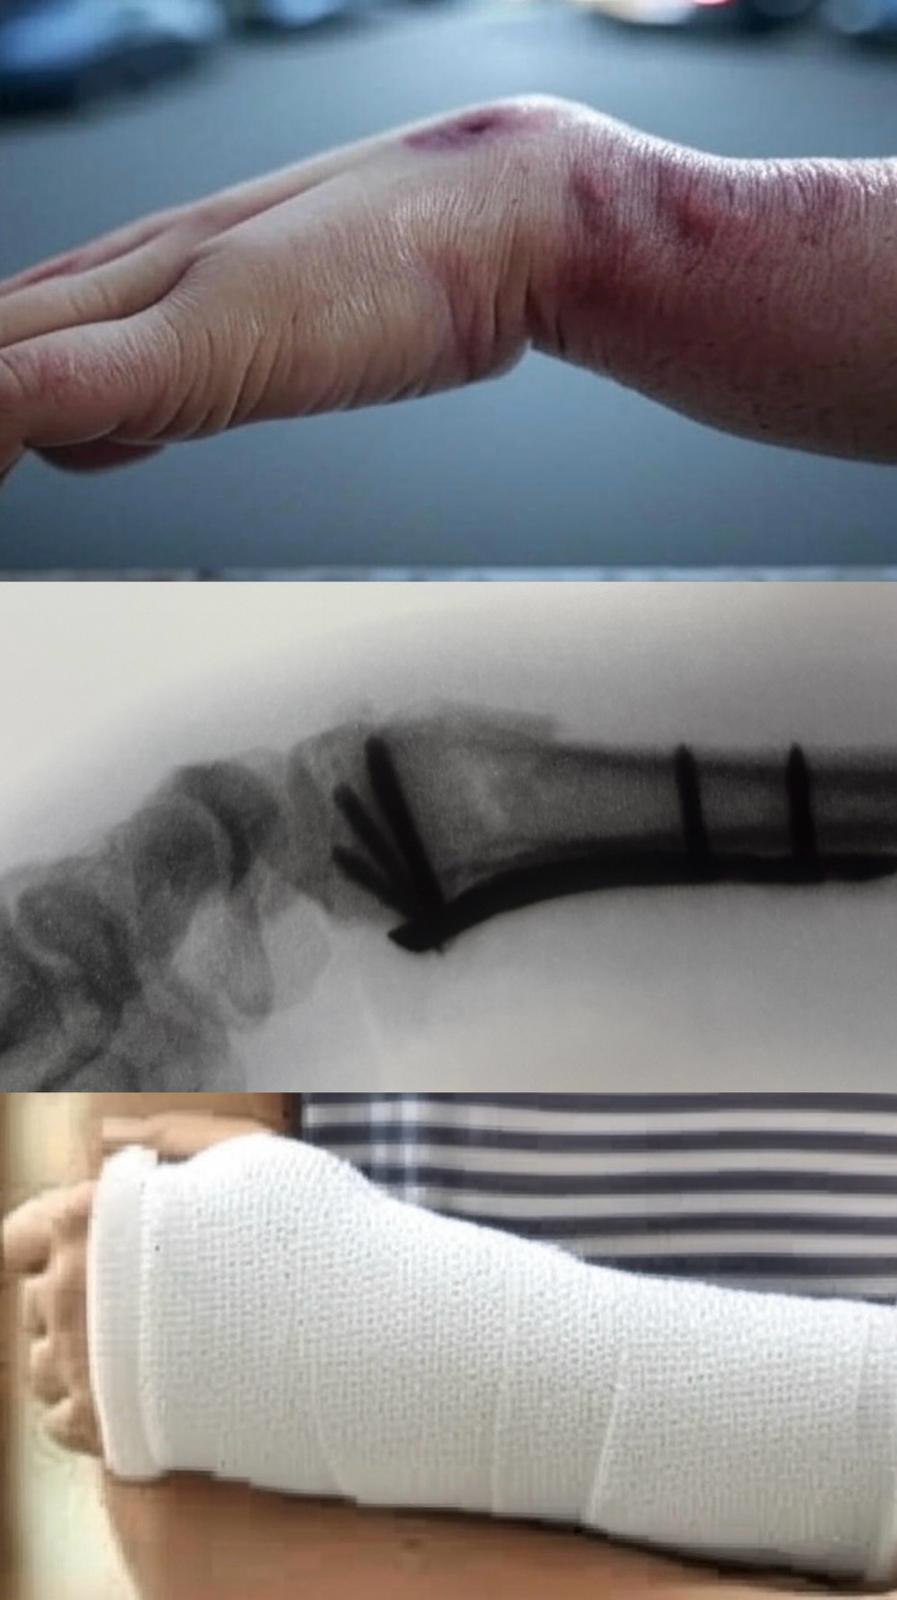

漫畫家阿信成為主筆後,日夜靠右手繪畫維生。某天,他在上班路上,遇見警察追捕疑犯。迎面而來的疑犯將他撞倒,他在本能反應下用右手撐地,結果導致遠端橈骨骨折並出現移位。事後他立即向骨科醫生求診,醫生首先在局部麻醉下進行骨折復位,再以石膏托臨時固定骨折。

由於右手是他的主力手,加上骨折屬粉碎性,故此醫生建議他接受手術,用鋼板來固定骨折。阿信明白右手的靈活性,對他的創作生涯至關重要,而打石膏卻未能達至骨折的精準復位,因此他決定接受手術。術後他的復康進度理想,很快便再次執筆出版漫畫!

與公務員對立的黑社會阿信,因誤入歧途而成為犯罪組織的骨幹成員。某天,他在路上被巡警攔截,便立即拔足狂奔,不但撞倒一名途人,為逃避警員追捕,他更從高處一躍而下,用右手撐地,以致手腕立時骨折變形。雖然他右手的傷勢嚴重,但身為通緝犯又怎會到醫院登記求診?結果他向跌打師傅求醫,手腕骨折以中藥外敷並用木板固定,他卻拒絕照X光來檢查骨折傷勢。

兩個月後,他發現手腕痛楚減輕,但變形卻沒有改善,關節也變得十分僵硬。原來遠端橈骨骨折,若不及早診治,會在骨折移位的情況下畸形愈合,影響手腕的活動和發力。要糾正卻需要做截骨手術,比起及早治療更為複雜。至於故事的結局,當然是離不開「邪不能勝正」的主旋律:阿信最終被捕、定罪和入獄;及後他被轉至羈留病房接受手術,使他可以在懲教署工場內,用已康復的右手,每日工作來回饋社會,從此社會也變得更安全!